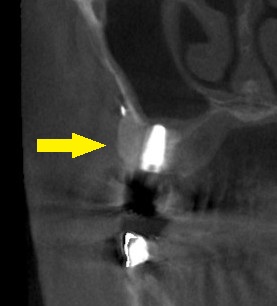

残存している骨に何とかインプラントを固定して、外側に人工骨を十分に填入し、人工膜で被覆して手術を終えました。

下の写真が、手術前後のCTです。